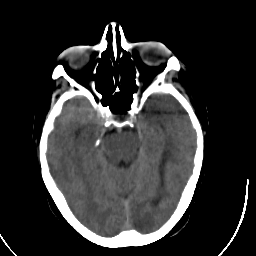

Stroke CT #3 -- Slice #8

[Home][Help][Clinical] Slice 8